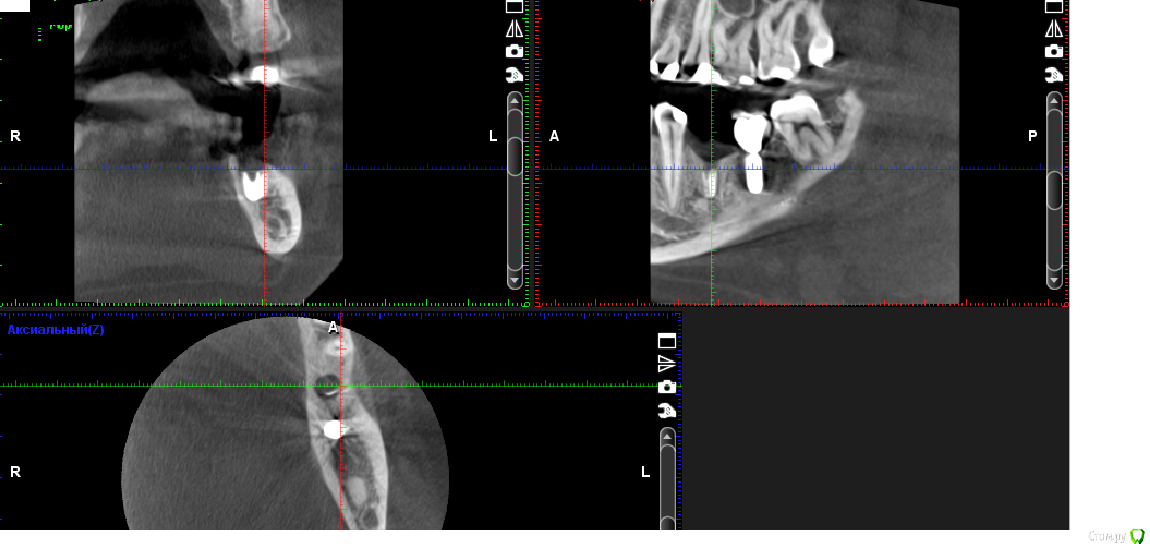

Марья Моревна Опубликовано 7 мая, 2017 Автор Поделиться Опубликовано 7 мая, 2017 Стоял 3 года, 4,0 на 9,0. Ушла платформа и один виток. Интеграция хорошая, периимплантита нет. Слом 3 недели назад,удаление абатмента неделю назад. Ссылка на комментарий

kamranchick Опубликовано 7 мая, 2017 Поделиться Опубликовано 7 мая, 2017 Стоял 3 года, 4,0 на 9,0. Ушла платформа и один виток. Интеграция хорошая, периимплантита нет. Слом 3 недели назад,удаление абатмента неделю назад.Вести на сгустке, через 2 месяца можете поставить имплантат. Обратите внимание еще на соседний имплантат. явно там не очень все хорошо. Ссылка на комментарий

kamranchick Опубликовано 8 мая, 2017 Поделиться Опубликовано 8 мая, 2017 Камранчик, Вы так советуете из-за риска перегрева при удалении? Или из-за обрастания эпителием лучше потом заново открыться? Аквариус, действительно фонит. Вот прицельный :более прогнозируемо будет, если сразу ставить имплантат то придется заглублять либо брать толще имплантат Ссылка на комментарий

Марья Моревна Опубликовано 8 мая, 2017 Автор Поделиться Опубликовано 8 мая, 2017 Толще и так лучше поставить : 4,5 или 5,0. А заглублять не хочется. Значит,имплантация+ аугментация сразу малопрогнозируемо?Как бы вывести язычную и вестибулярную стенки в одну горизонталь,чтоб не было горки? Может,прикрыть сгусток мембраной? Или это уже потом? Реабилитация затягивается...Кроме того,толщина язычной стенки 2,4 мм.Значит, новый центр лучше сместить вестибулярнее? Ссылка на комментарий

kamranchick Опубликовано 8 мая, 2017 Поделиться Опубликовано 8 мая, 2017 Толще и так лучше поставить : 4,5 или 5,0. А заглублять не хочется. Значит,имплантация+ аугментация сразу малопрогнозируемо?Как бы вывести язычную и вестибулярную стенки в одну горизонталь,чтоб не было горки? Может,прикрыть сгусток мембраной? Или это уже потом? Реабилитация затягивается...Кроме того,толщина язычной стенки 2,4 мм.Значит, новый центр лучше сместить вестибулярнее?На мой взгляд вообще хорошо связать эти 2 имплантата, чтобы они не по одиночке работали. язычную стенку можно спилить, чтобы было ровно. Ссылка на комментарий